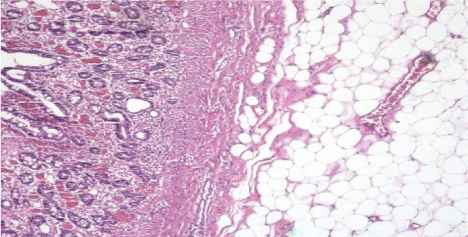

The patient then underwent exploratory laparotomy and multiple, giant lipomas could be palpated in second, third, fourth part of duodenum and proximal jejunum. Duodenum 4 cm distal to ampulla was excised along with 14 cm of proximal jejunum [Table/Fig-4]. Intestinal continuity was maintained by end-to-end duodenojejunal hand-sewn anastomosis. The postoperative period was uncomplicated and she was discharged from the hospital successfully. Final histopathological diagnosis of the specimen were multiple, submucosal lipomas vary from 1.3 × 1.3 × 1.0 cm to 11.0 × 5.0 × 4.0 cm [Table/Fig-5].

Pathological report indicating duodenal lipoma originating in submucosal layer (H&E 4x).

According to our study, as shown in [Table/Fig-9], lipomas tend to be noted mostly in the second part of the duodenum. The majority of the DLs arise from the submucosa [3,4] but may extend through the bowel wall and into the serosal or mesenteric fat. DL presents as a round or ovoid, soft mass with regular or lobulated contours. They can be either sessile or pedunculate. The overlying mucosa of the duodenal lipoma is usually normal, but there may be areas of ulceration or erosion. Multiple DL is very rare, there is only 11 cases reported so far including our case.